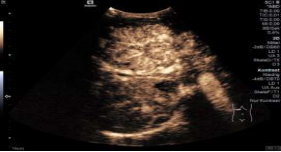

*星形模块的剪切波成像Sequoia比传统超声高出6倍的能量,获取到优异的图像分辨率和均一性。